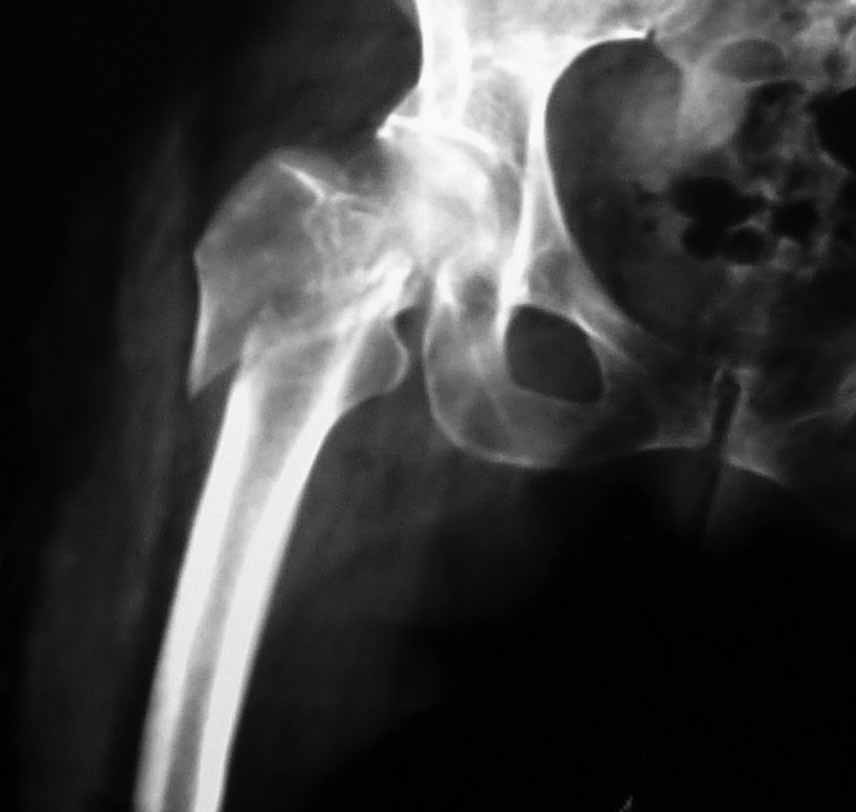

Пациентка 53 лет. ДТП 09.01.12: сочетанная травма: перелом 2-5 ребер справа, ушиб легких; перелом обеих лонных костей без смещения; закрытый перелом проксимального конца правой бедренной кости; открытый оскольчатый внутрисуставной перелом проксимальных концов костей правой голени.

В нашей клинике 11.01 выполнен минимально инвазивный остеосинтез большеберцовой кости (снимки до операции не перефотографировал) с пластикой перемещенными лоскутами дефекта, образовавшегося вследствие некроза кожи на передней поверхности голени. Бедро одномоментно делать не стал, не было уверенности в наличии перелома на уровне шейки. Во время операции смотрел тазобедренный сустав под ЭОПом, головка неподвижна. После операции повторили КТ, стало очевидно, что имеется субкапитальный перелом.

Хочу еще раз переспросить: расчитан ли проксимальный бедренный гвоздь на фиксацию субкапитальных переломов? На сайте производителя PFNA (http://www.synthes.com/MediaBin/International%20DATA/036.001.143.pdf) медиальные переломы шейки бедренной кости перечислены в противопоказаниях.

И еще: не явится ли препятствием для введения гвоздя дугообразный изгиб диафиза бедренной кости? Вершина деформации расположена на 110мм дистальнее проксимального края малого вертела. Это я по КТ измерил точно. Можно, конечно, думать о короткой ножке. Но обеспечит ли она достаточную фиксацию при таком переломе?